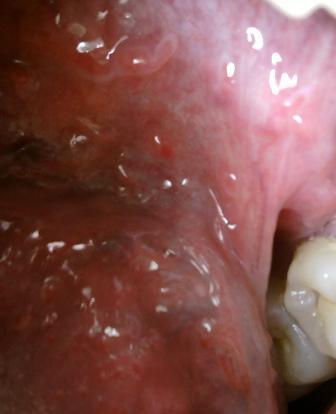

感染尖锐湿疣病毒之后会立即发病吗尖锐湿疣是一种病毒性及逼供,感染病毒之初,并不会立即发病,而是有一定时间的潜伏期,一般是三个月左右的时间,尖锐湿疣会复发,常常让很多患者痛苦不已,为了让尖锐湿疣的危害早点消除,做到早预防、早治疗,尖锐湿疣的发病多是因为直接发生不洁性行为或间接接触被感染物而致病。